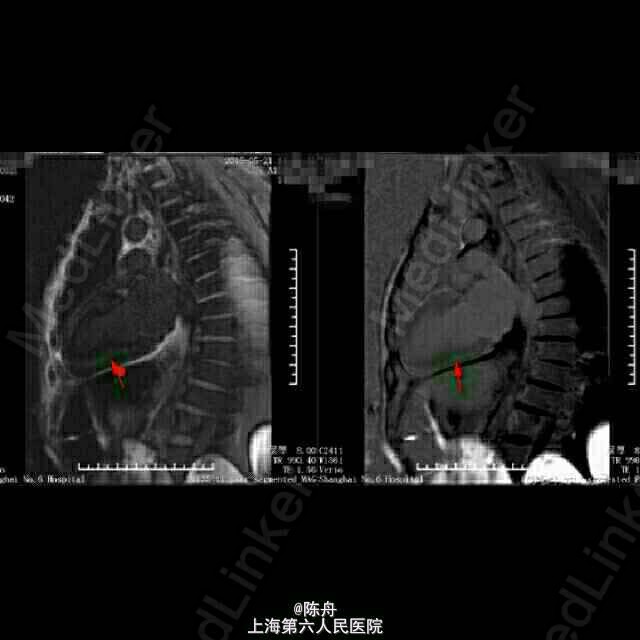

查体:BP 90/60 mmHg,神志清醒,气平,无贫血貌,颈静脉怒张,舌头正常,双肺听诊呼吸音清,双肺未及干啰音。心浊音界大致正常,心率74次/分,律齐,P2=A2,心音减低,各瓣膜区未闻及病理性杂音。腹壁柔软,无腹部压痛,肝脾未触及。双下肢轻度水肿。无关节肌肉疼痛。 辅助检查: 血常规:白细胞 6.7 *10^9/L ,血红蛋白 120 g/L ↓,血小板 218 X10^9/L ,中性细胞百分比 46.5 % 。血沉: 34 mm/h 。C反应蛋白 8.53 mg/L ↑。 肝肾功能:总蛋白 44 g/L ↓,白蛋白 29 g/L ↓,谷丙转氨酶 43 U/L ,谷草转氨酶 72 U/L ↑,总胆红素 9.0 μmol/L ,直接胆红素 5.5 μmol/L ,总胆汁酸 3.1 μmol/L ,前白蛋白 170 mg/L ↓,总胆固醇 2.40 mmol/L ↓,甘油三脂 1.38 mmol/L ,高密度脂蛋白 0.48 mmol/L ↓,低密度脂蛋白 1.48 mmol/L ↓,肌酸激酶 194 U/L ↑,CK-MB 16.0 U/L ,乳酸脱氢酶 334 U/L ↑,α羟丁酸脱氢酶 282 U/L ↑,血清钾(干式) 3.3 mmol/L ↓,血清钠(干式) 134 mmol/L ↓,血清氯(干式) 91 mmol/L ↓,钙(干式) 1.94 mmol/L ↓,尿素(干式) 19.0 mmol/L ↑,肌酐(干式) 87 μmol/L。 血气:PH 7.40 ,二氧化碳分压 39.7 mmHg ,氧分压 79.8 mmHg 生化报告:清蛋白 49.2 % ↓,α1球蛋白 8.6 % ↑,α2球蛋白 18.6 % ↑,β1球蛋白 6.3 % ,β2球蛋白 2.9 % ↓,γ球蛋白 14.4 % 。 免疫:血清KAPPA轻链 2.80 g/L ,血清LAMBDA轻链 0.26 g/L ↓,κ/λ比值 10.81 ↑。 免疫:尿KAPPA轻链 1260.00 mg/L ↑,尿LAMBDA轻链 4.62 mg/L ↑。 其它免疫指标全阴性. 甲状腺功能:游离T3 2.81 pmol/L ↓,游离T4 19.94 pmol/L ,促甲状腺激素 2.71 mIU/l 。 生化:肌钙蛋白-I 0.305 ↑,CKMB 9.6 ug/L ↑,B型钠尿肽(BNP) 1260.00 ng/L ↑。B型钠尿肽前体(proBNP) >35000 ng/L ↑。 心脏超声: 1.左心房稍扩大2.左室壁增厚3.未见节段性室壁运动异常。EF:60% 24H动态心电图:1.窦性心律2.房性早搏(时呈成对,代偿后见室性逸搏)3.房性心动过速(短阵)。终止后呈窦性,交界性逸搏,恢复时间<2秒。4.室性早搏(多源性,时呈成对,二联律)5.ST段下移,T波倒置(持续性:第一,三通道导联,呈水平型)6.未见传导异常。 心脏 MRI:1.双心室壁增厚,收缩功能保留,心肌淀粉样变可能。2.微量心包积液,少量双侧胸腔积液。 胸部CT:1.慢性支气管炎,两肺多发微小结节,考虑炎性肉芽肿可能。2.心脏增大,两侧胸腔积液,伴下肺膨胀不全。 电子胃镜:糜烂性浅表性胃炎。病理:阴性。

随访:1周后失联 淀粉样变(Amyloidosis)是指不溶性蛋白质沉积在组织或器官并导致其功能异常的一组疾病。1853 年病理学家 Virchow 发现了一种嗜酸性均匀一致的物质沉积在组织或器官中,因这种物质对碘的颜色反应与淀粉相似而命名为“淀粉样物质”,并将由于此类物质沉积所导致的一组疾病称为淀粉样变。近四十年研究证实此类物质是蛋白质,而非淀粉样碳水化合物,但至今仍沿用“淀粉样变”这一术语。 淀粉样变可以影响多系统器官,尤其以肾脏、心脏、肝脏、神经、胃肠道等病变严重,也可以累及肌肉和骨关节。目前淀粉样变的分类较为混乱,尚没有统一、完善的分类。根据临床特点,淀粉样变可以分为系统性或局灶性,获得性或遗传性。获得性系统性淀粉样变包括:AL(原发性)、AA(继发性、反应性)和 Aβ2-M(透析相关性)。 淀粉样变的病因不同,病理形态学改变却拥有共同的特征。现已证实,淀粉样变沉积物质具有共同的核心结构,即与淀粉样物质长轴垂直的反平行β折叠层片样结构。这种空间组织形式决定了它与刚果红染色的高度亲和力。偏光镜下,被刚果红染色的淀粉样沉积物质出现苹果绿色双折射光,这是淀粉样变病理学诊断要点。 心脏受累可导致心脏肥大、心律失常和心力衰竭,是 AL 淀粉样变患者最常见的死因。 治疗的主要原则是减少/干预前体蛋白合成,稳定前体蛋白的自身结构,破坏淀粉样蛋白的稳定性,以及积极对症处理。 该患者为67岁男性,发病以右心功能不全为主要表现:颈静脉怒张,胃肠淤血,双下肢水肿,实验室检查:肌钙蛋白-I 0.305 ↑,CKMB 9.6 ug/L ↑,B型钠尿肽(BNP) 1260.00 ng/L↑,B型钠尿肽前体(proBNP) >35000 ng/L ↑,血清κ/λ比值升高,尿中有大量KAPPA轻链,肝肾功能及其它免疫指标大致正常;心脏超声示左心房稍扩大,左室壁增厚,EF:60%。心脏MRI示双心室壁增厚,收缩功能保留,心室肌细胞间可见颗粒样物质沉积。结合患者临床表现及实验室检查,及肾内科、内分泌、血液科会诊意见,考虑心脏淀粉样变。若条件容许,可进一步行右心导管术及心内膜活检以明确诊断。该患者入院第二天即出现血压下降,多巴胺维持;入院第四天出现心率下降,心电图由入院前窦性心律,肢体导联低电压,T波改变(V3~V6倒置),变为:交界性逸搏节律,逸搏-夺获二联律,给予异丙肾上腺素维持心率。积极对症处理无效,患者及家属放弃继续治疗。 【经典病例,仅供内部学习,请勿刊发】 【感谢各位同道点评和指教】